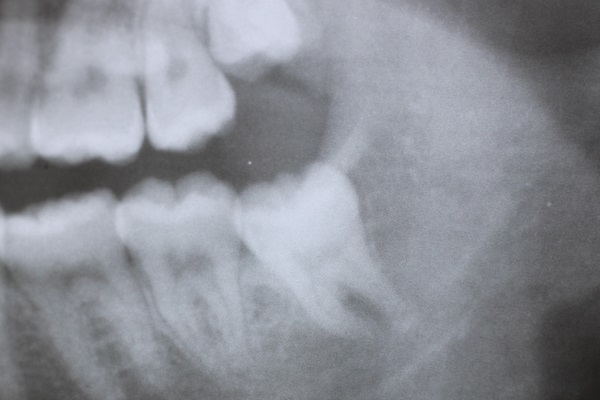

7親知らず

Case7